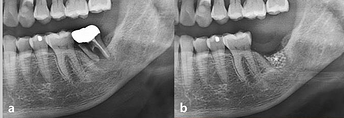

Case photos provided by: Customized three-dimensional printed ceramic bone grafts for osseous defects: a prospective randomized study.

Serial clinical and radiographic images of the experimental group receiving customized 3D-printed ceramic bone grafts. (a ) preoperative panoramic radiograph of tooth #37; (b ) postoperative panoramic radiograph after surgical extraction of tooth #37 with GBR using OSTEON 3D and Collagen Membrane; white asterisk indicates grafted bone material; (c ) CBCT image before the implant placement at visit 5; (d ) panoramic radiograph after implant fixture installation; (e ) panoramic radiograph after final implant final prosthesis; (f ) clinical photo of bone grafting; (g ) 3D digital image of design for fabrication of customized 3D printed ceramic bone grafts (OSTEON 3D).